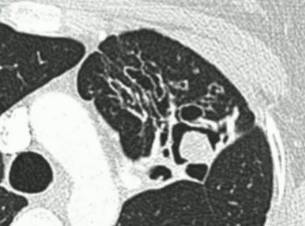

慢性空洞性肺曲霉病(CCPA):最常见,单发或多发的肺空洞(薄壁或厚壁),空洞内可包含一个或多个曲菌球或不规则的腔内物质,具有曲霉菌血清学和微生物学依据,并有明显肺部和全身症状,至少3个多月的观察有放射影像学进展(新发空洞,空洞外周浸润增加及纤维增生增加)。

亚急性侵袭性肺曲霉病(SAIA):轻度免疫缺陷的侵袭性肺曲霉病患者,发生在1-3个月内,具有可变的影像学特征,包括空洞、结节、有“脓肿形成的进展性实变”。最重要的特征为肺组织发现菌丝,另血液或呼吸液GM试验呈强阳性。